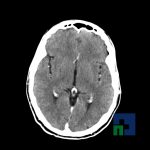

- Accidentelor vasculare cerebrale ischemice sau hemoragice

- Evaluarea deplasării liniei mediane

- Diagnosticul edemului cerebral, a contuziei cerebrale, a leziunilor axonale difuze edematoase/hemoragice, a dilacerării cerebrale, a hematomului intraparenchimatos posttraumatic, a hematoamelor subdurale/extradurale (acute, subacute, cronice), a hemoragiei intraventriculare, a hemoragiei subarahnoidiene